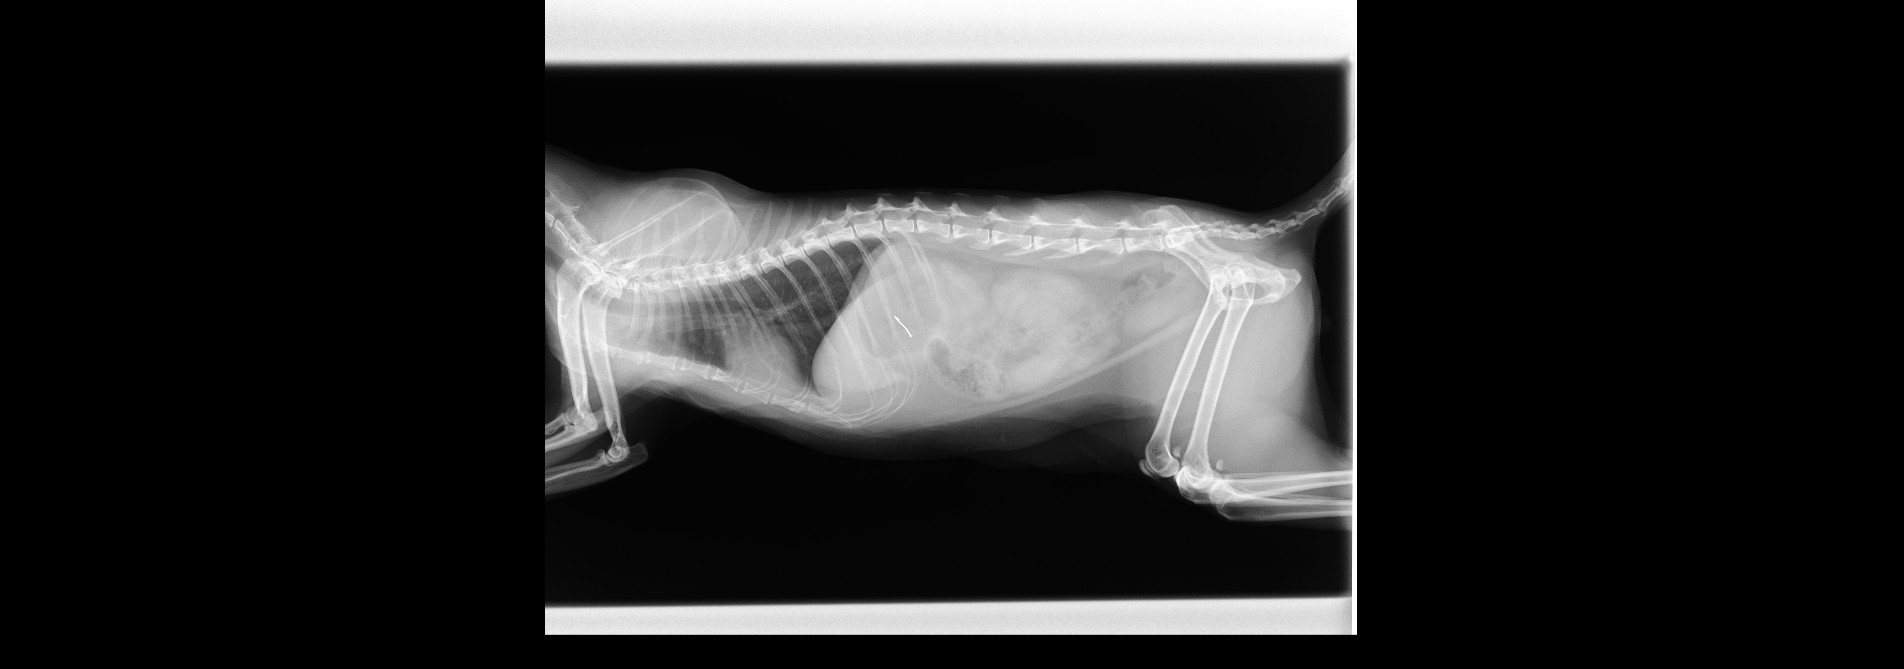

猫の尿管結石(尿管膀胱側側吻合)

猫の会陰尿路造瘻術

猫の鼻腔内リンパ腫

猫の尿失禁について

腸内の紐状異物

仙腸関節脱臼

肘頭骨折